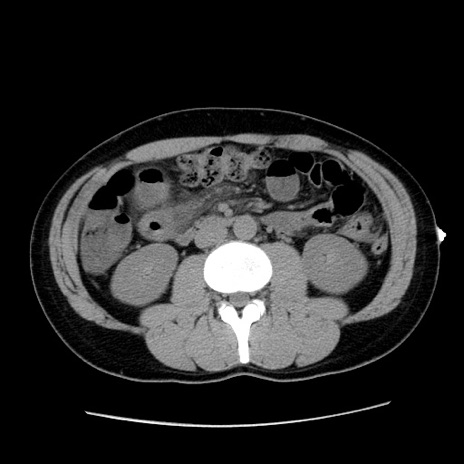

症例36(横断像)

【症例】20歳代 男性

【主訴】心窩部痛

【現病歴】今朝より上腹部痛あり。一旦軽快していたが再度出現したため救急要請。昨日夕に白身の魚を含む刺身を食べた。

【身体所見】BP 136/89mmHg、HR 74/min、BT 37.0℃、腹部:膨満、軟、心窩部に圧痛あり。反跳痛なし、筋性防御なし、腸雑音やや亢進あり。

【データ】WBC 17700、CRP 0.48